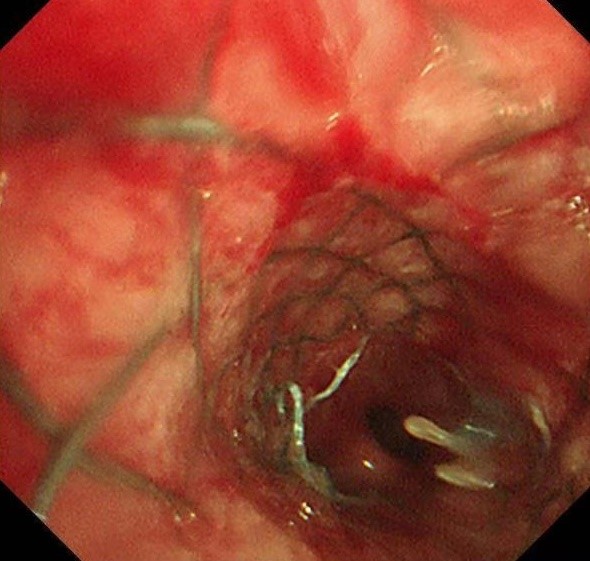

术中发现,右主支气管完全闭塞,肿瘤新生物广泛浸润;左主支气管混合性狭窄,狭窄率高达70%,并伴有黏膜浸润样改变。团队冷静而高效地操作,仅用不到1分钟便将支架精准置入目标位置。置入的可过活检孔道气管支架成功打开了左侧主支气管,同时确保上下叶开口通畅。患者呼吸困难立即减轻,胸闷气促的折磨被迅速解除。术后,丁女士激动地拉着蒋军红主任的手,激动着说:“已经三天三夜没能躺下睡觉了,谢谢你们让我又能喘口气!”

此次救治中,蒋军红主任团队采用了自主研发的TTS技术(Through-The-Scope)气道支架。这种技术与传统的导丝引导气道支架相比,具有以下显著优势:

·操作简便、高效安全:支架植入可以在软性支气管镜下快速完成;

·精准定位:尤其适用于复杂性气道狭窄病例。